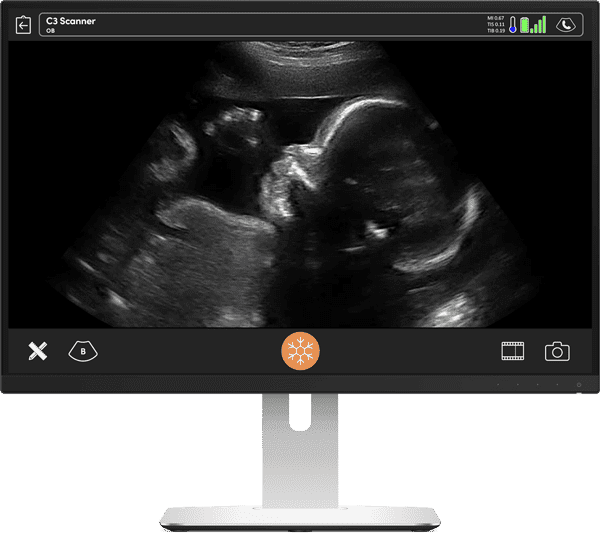

妊娠初期のけいれんや出血を呈する患者では、胎児の生存可能性をタイムリーに確認することが重要です。クラリアス C3 HD3 を使用すると、胎児の心臓を簡単に識別でき、心臓の動きで生存性を確認できます。